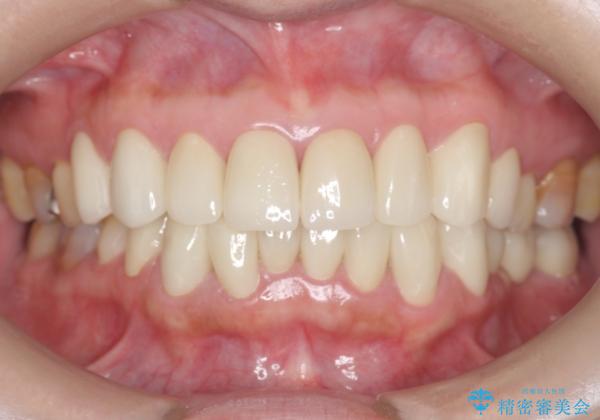

- 前歯の色や形を全体的に綺麗したいといらっしゃった方の症例です。

上顎は左側 4 番目から右側 4 番目までの 8 歯をオールセラミッククラウンで補綴しました。

下顎は左側 4 番目から右側 4 番目までの 8 歯と左下 567 ブリッジをオールセラミッククラウンで補綴し、右下67の銀歯はセラミックインレーによる修復を行いました。

今回用いたオールセラミッククラウンはジルコニアフレームという白い素材の上にセラミックを盛っているため、審美性が非常に高いのが特徴です。

また、ジルコニアは人工ダイヤモンドの材料にも使われているほど高い強度を持っており、そのためオールセラミッククラウンは審美性だけでなく、奥歯やブリッジの補綴も可能とするクラウンです。